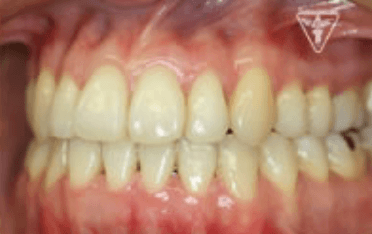

20代女性:オープンバイト(開咬)をゴムメタルにて矯正治療したケース

治療前後の比較

治療前、装置装着直後

治療後